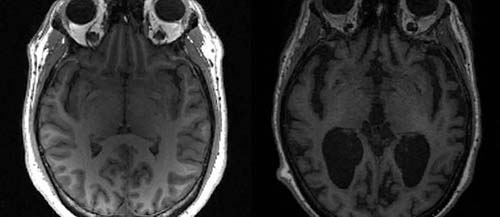

O nível baixo de testosterona em homens com mais idade pode estar ligado a um risco aumentado de demência e alzheimer. É o que sugere um estudo envolvendo quase 160 mil pessoas publicado na revista científica Alzheimer's and Dementia. Os pesquisadores da Universidade da Austrália Ocidental em Perth não encontraram um nexo causal para explicar a natureza relação do baixo nível do hormônio com a chance aumenta das doenças, mas o artigo apresenta evidências robustas dessa conexão.

Depois de ajustar para outras variáveis, os pesquisadores descobriram que os homens com mais idade e com testosterona mais baixa eram significativamente mais propensos a ter demência e Alzheimer.

Os pesquisadores não têm certeza se a testosterona de fato protege contra a demência e o Alzheimer. No entanto, não é a primeira vez que esta relação é estabelecida em trabalhos científicos. Outros estudos anteriores já mostravam tal conexão. Além disso, sabe-se que a maioria das pessoas que vivem com alzheimer são mulheres, mais um indício de que um nível de testosterona mais elevado seria um fator protetor.